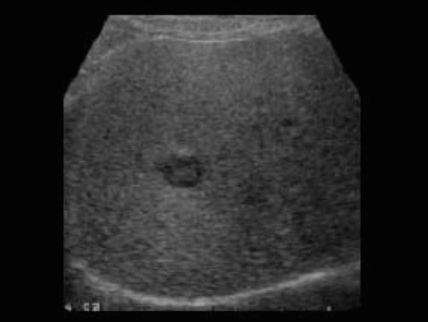

US finding

- comet-tail artifact

- 크기가 작고 간전체에 흩어져 보임(multiple small hyperechoic lesion)

- echos scattered through the liver ( <1cm )

bile duct hamartomas ④ caroli disease